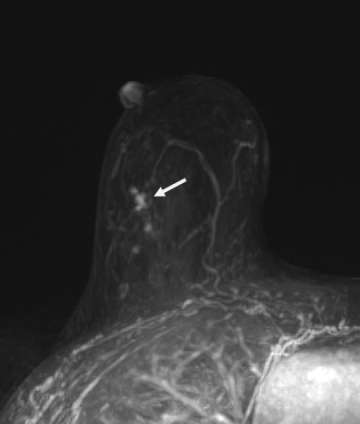

Calcifications are best visualized on mammography, and thus this modality plays a crucial role in screening for DCIS; however other imaging modalities may also provide additional information that can suggest a diagnosis of DCIS. Ultrasound may be utilized when calcifications are identified on mammogram to look for solid components, which may aid in ultrasound-guided biopsy. On ultrasound, calcified DCIS may appear as echogenic foci within a mass or duct. Noncalcified DCIS may have a similar appearance, but without posterior acoustic shadowing. In addition, internal vascularity can also help to improve the positive predictive value.7 On MRI, enhancement patterns play a large role, with linear or segmental non-mass enhancement most commonly associated with DCIS, regardless of MRI kinetics (Figure 2).8

Case: Ductal Carcinoma In Situ Figure 2

Figure 2 (White Arrow): Linear enhancement pattern at site of biopsy-proven DCIS.